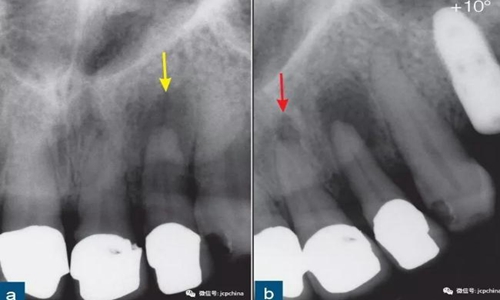

第一張根尖片22牙(黃色箭頭)的根尖周透射影清晰可見。第二張根尖片(水平遠中方向偏移10°)顯示21牙的根尖周“透射影”(紅色箭頭)。此“透射影”實際上是切牙孔,該解剖噪點和根尖周透射影的表現(xiàn)類似。

所以,經(jīng)驗不足的臨床醫(yī)生很容易誤診。